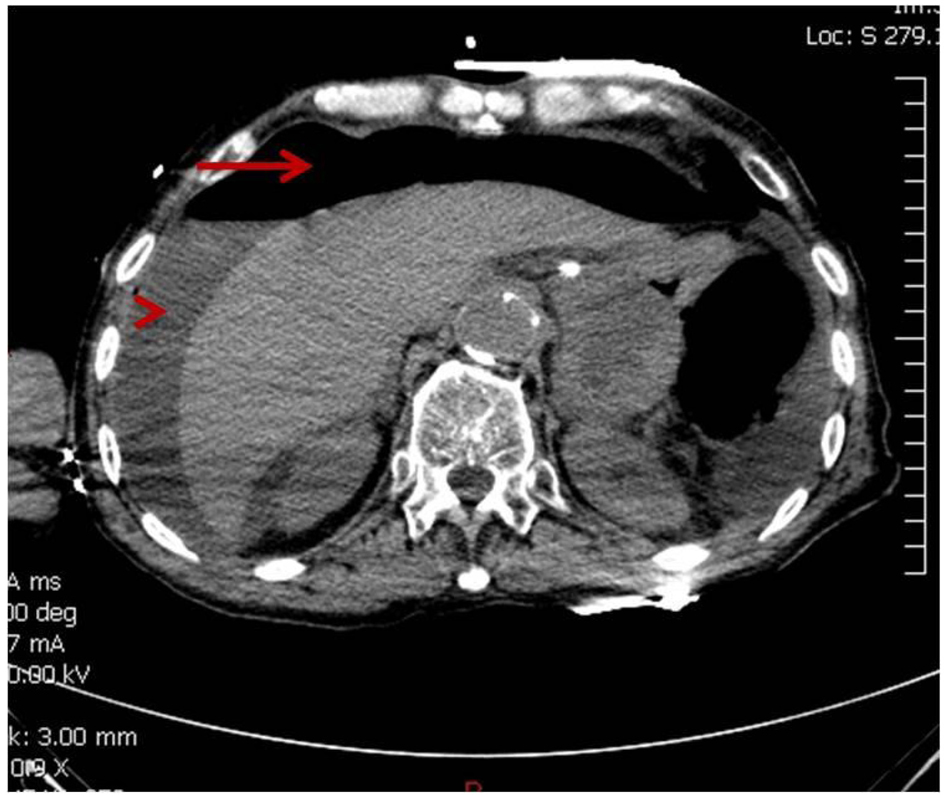

At the beginning of the second cycle, the patient came to the hospital for radiation and complained of severe abdominal pain but was sent home with analgesics. The next day he came back to the emergency room with persistent severe abdominal pain, accompanied with decreased appetite and diarrhea. Abdominal X-ray showed questionable free air in the abdomen, so a non-contrast CT scan was performed to clarify. CT scan revealed the development of moderate pneumoperitoneum and perihepatic fluid (Fig. 2). Patient went into cardiac arrest and was resuscitated, but required ventilator support. Due to the overall critical condition, no surgical intervention was performed. He expired 6 h after he arrived at the emergency room.

![]() Click for large image | Figure 2. CT showing moderate pneumoperitoneum (arrow) and perihepatic fluid (arrow head). |